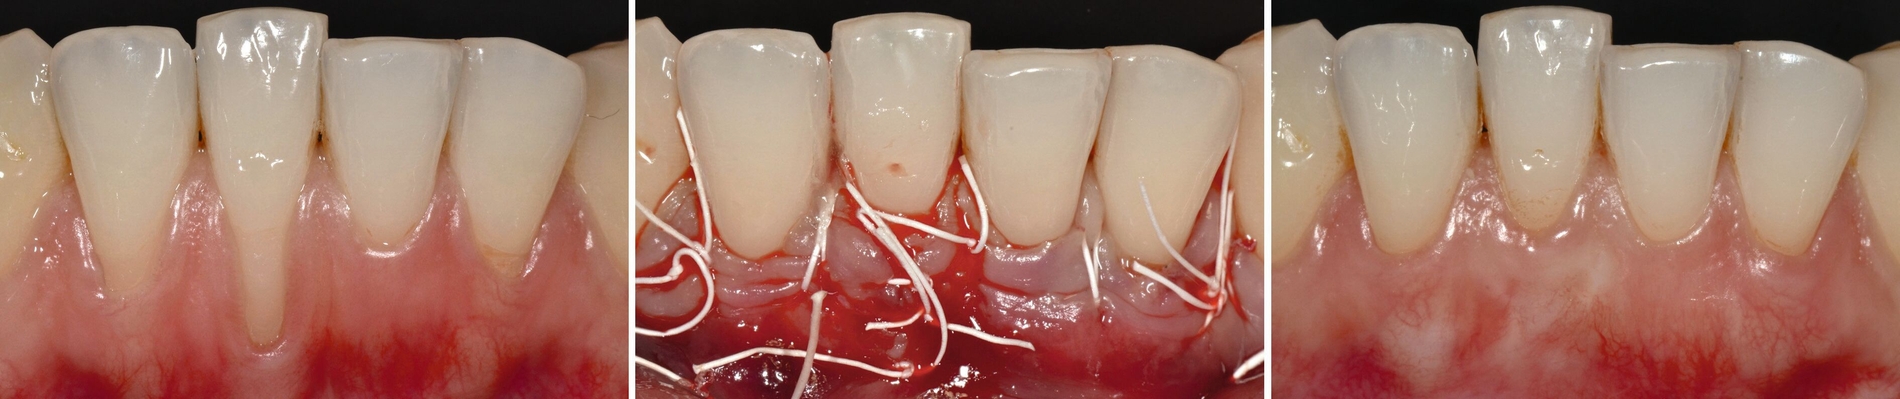

Fortgeschrittener Fall für eine chirurgische Rezessionstherapie (Abbildung 6): Die Patientin war zum Zeitpunkt der Erstuntersuchung 30 Jahre alt, der Auslöser für die Behandlung war ein Fortschreiten der Rezessionen bei den Zähnen 44 und 43 sowie eine starke Dentinüberempfindlichkeit. Es gab keinerlei Allgemeinerkrankungen oder Allergien. Die Mundhygiene war sehr gut, kein Nikotinabusus. Die Zähne 44 und 43 waren nicht gelockert und vital. Oberflächlich bestand eine leichte Karies. Die parodontale Rezession war ein Defekt der Cairo-Klasse RT1 bei Zahn 44 (Rezessionstiefe: 3 mm), RT2 bei Zahn 43 (4 mm tief). Die Deckung der Rezession erfolgte hier mit einem koronal verschobenen Tunnel (Verschiebelappen) und Bindegewebstransplantat. Die Rezessionen waren auch nach fünf Jahren noch vollständig gedeckt (Abbildung 7).